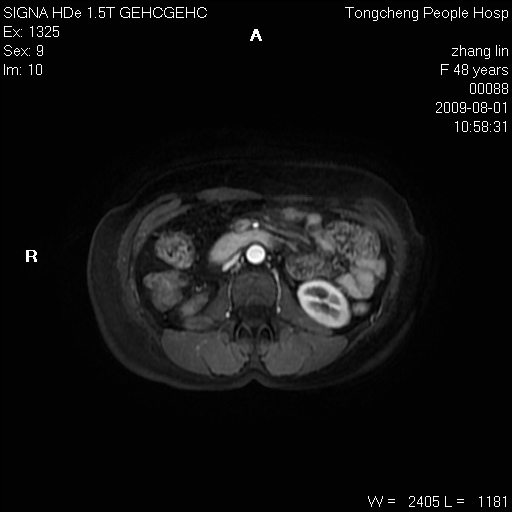

女,48岁。健康体检,彩超发现右肾占位性病变。平素健康。

临床诊断:右肾占位性病变,性质待定(囊肿?肿瘤?)。

上中腹部mr平扫+增强扫描,图像如下:

右肾上极见一类圆形病灶,t1wi呈等信号t2wi呈等高混杂信号,三期增强无强化,边界清---考虑囊肿出血。

同反相位均表现为等信号,病变无强化,考虑含蛋白的囊肿可能,弥散加权相或许有些帮助,

慢性胆囊炎